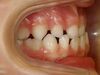

Manque de place pour l'évolution des incisives définitives inférieures

Le manque de place à l’arcade inférieure peut empêcher les dents définitives d’évoluer normalement. Ceci peut se traduire par deux situations cliniques :

• un encombrement antérieur important (« chevauchement » ou évolution des incisives latérales en arrière des incisives centrales) ;

• la perte prématurée de dents de lait. Sur la photo, trois incisives définitives ont fait tomber quatre incisives temporaires. Il peut arriver que quatre incisives définitives fassent tomber les quatre incisives de lait, et une ou deux canines de lait. Dans ce cas, les dents paraissent alignées mais il existe malgré tout un manque de place important.

Pourquoi traiter ?

Un traitement précoce permet aux dents définitives d’évoluer normalement, et peut permettre d’éviter les traitements avec extraction de dents définitives à l’adolescence.